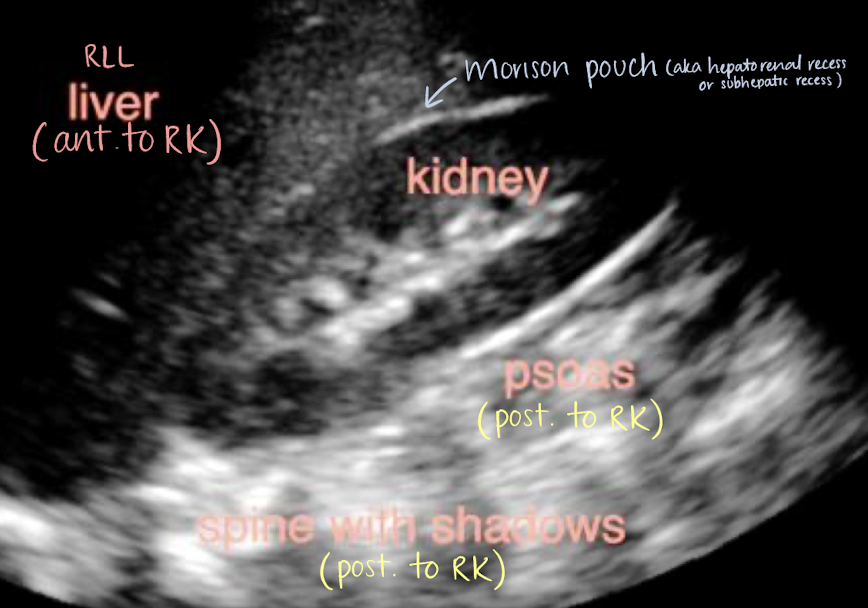

structures anterior to the RK and LK

anterior to RK

right adrenal gland

RLL

Morison’s pouch

2nd part of duodenum

hepatic flexure of colon

aka hepatorenal recess or subhepatic recess

space between liver and RK

patients may have ascites here

right posterior subhepatic space located anterior to kidneys and inferior to liver where fluid may collect